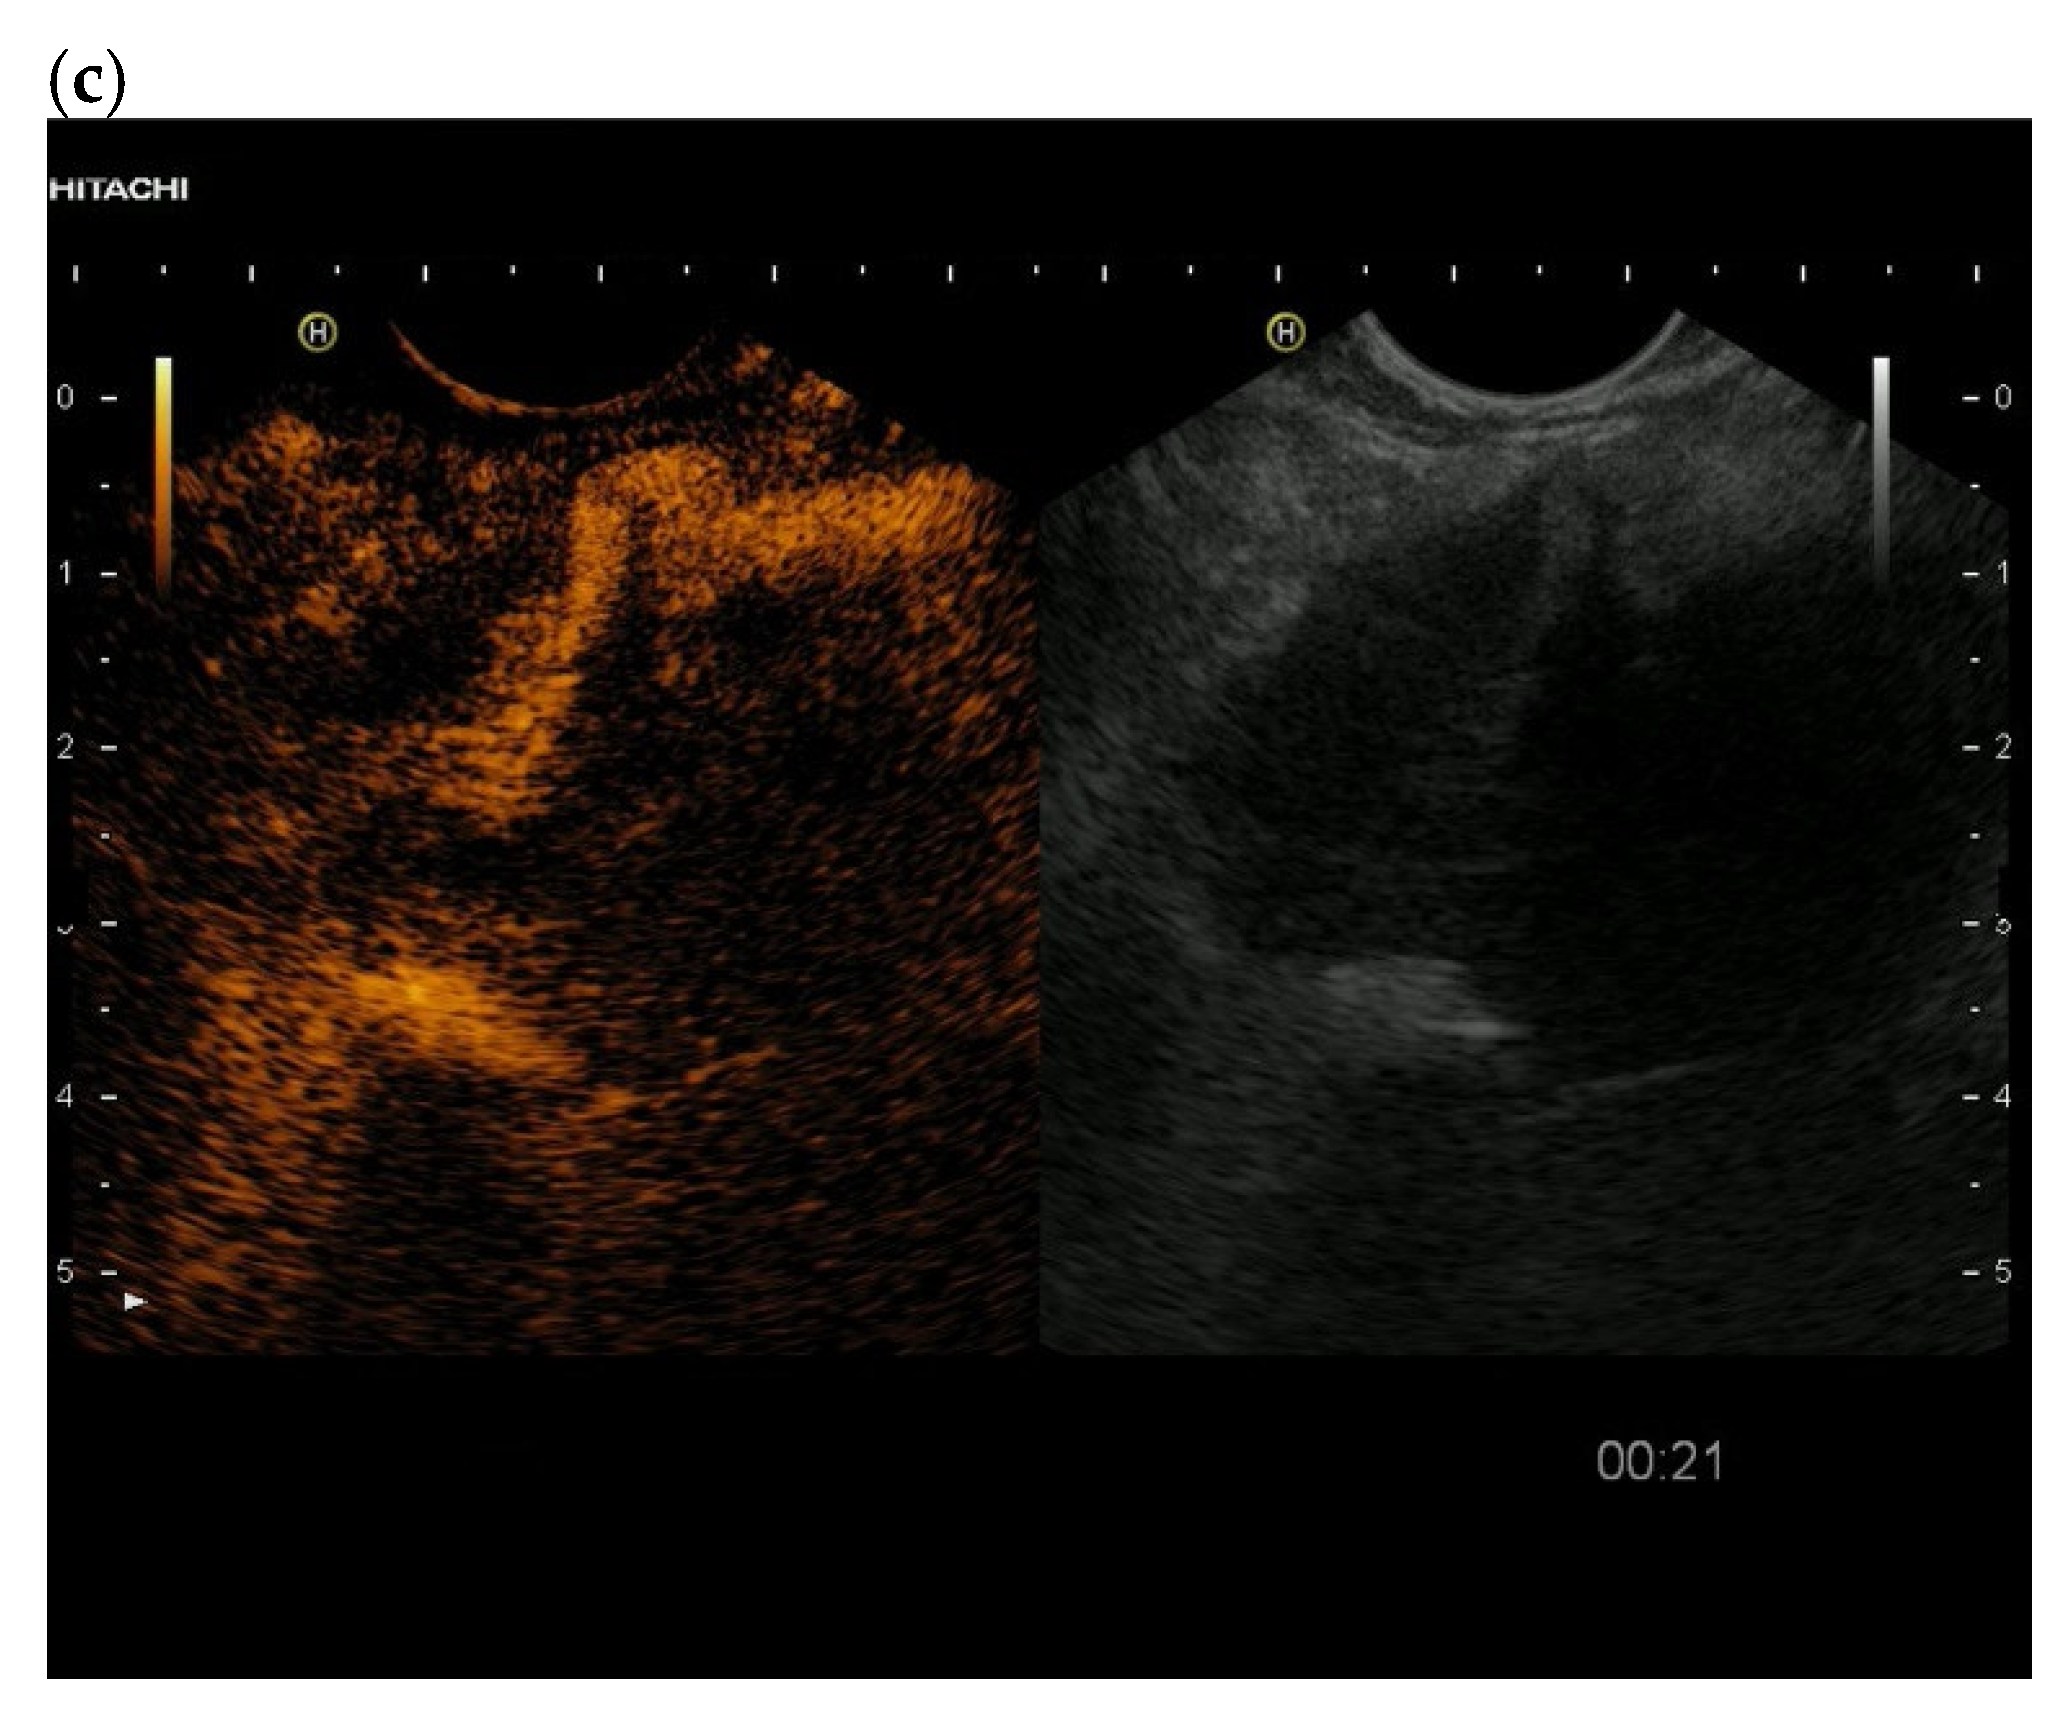

3.4. CEUS and CH-EUS

| Cases | CEUS | CH-EUS | ||

|---|---|---|---|---|

| Arterial Phase | Venous Phase | Arterial Phase | Venous Phase | |

| RCC metastases [83] (n = 4) | Hyperenhancement, Early | Hyperenhancement | ||

| RCC metastases [61] (n = 3) | Hyperenhancement, homogeneous pattern | Slow washout | ||

| RCC metastasis [86] (n = 1) | Hyperenhancement, Inhomogeneous pattern | No washout | ||